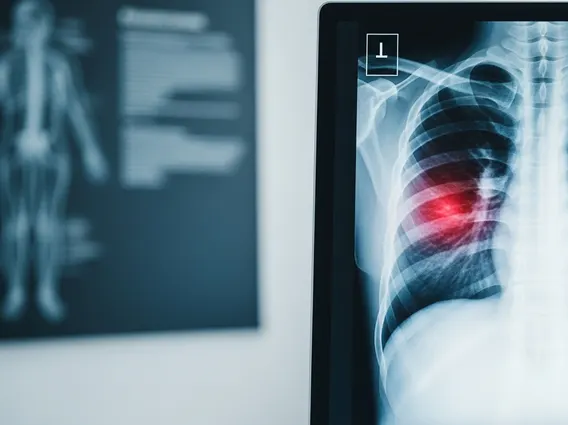

Further diagnostic tests may include an electrocardiogram (ECG) to assess heart activity, blood tests (e.g., cardiac enzymes to check for heart damage), chest X-rays to visualize the lungs and heart, or more advanced imaging like CT scans or MRI. Endoscopy may be performed to investigate gastrointestinal causes, while stress tests or angiograms can evaluate cardiac blood flow. The goal is to gather sufficient thoracodynia chest pain info to accurately identify the underlying condition.